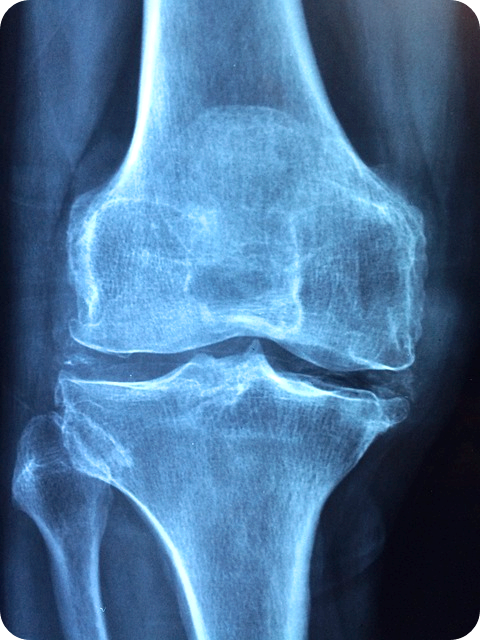

- X-레이 및 MRI: 관절 구조와 염증 부위를 시각화하기 위한 영상 검사입니다.